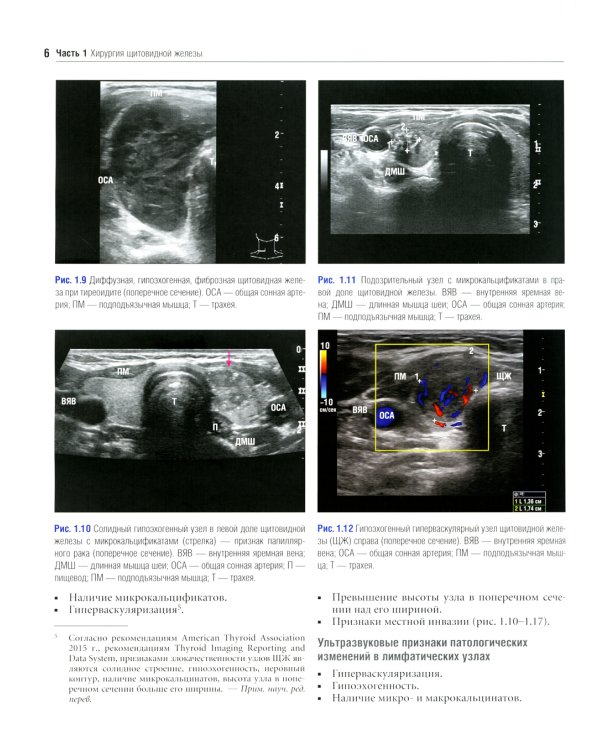

Данное издание представляет собой великолепно иллюстрированный хирургический атлас. В нем рассмотрены методы ультразвукового исследования шеи, молекулярно-генетическое тестирование пациентов с узловыми образованиями в щитовидной железе, робот-ассистированные хирургические методы, техника эндоскопических операций при эндокринных опухолях, хирургия при рецидиве заболевания, аутотранснлантация и криоконсервация околощитовидных желез, адреналэктомия при метастазе в надпочечнике, хирургия нейроэндокринных опухолей тонкой кишки и их метастазов в печени. «Атлас эндокринной хирургии» состоит из 4 частей: «Хирургия щитовидной железы», «Хирургия околощитовидных желез», «Хирургия надпочечников», «Хирургия опухолей поджелудочной железы и карциноидов». Всего в издании 29 глав, подготовленных сотрудниками экспертных факультетов ведущих медицинских школ США, Европы и Азии. Каждая глава состоит из разделов, в которых описаны общие сведения, показания и противопоказания, оценка риска, алгоритм принятия решений и планирование вмешательства, необходимое оборудование и материалы, хирургические техники, результаты лечения, осложнения и последующее наблюдение, а также даны советы и предостережения авторов. В книге много информации, которой нет в других источниках. Наряду с многочисленными фотографиями, сделанными в ходе операций, а также данными, полученными при различных методах визуализации, приведено значительное количество иллюстраций и видеоматериалов, демонстрирующих хирургическую технику или обследование. Издание предназначено практикующим врачам в области эндокринной хирургии, специалистам в смежных областях медицины и студентам медицинских высших учебных заведений.| Издательство | Логосфера |